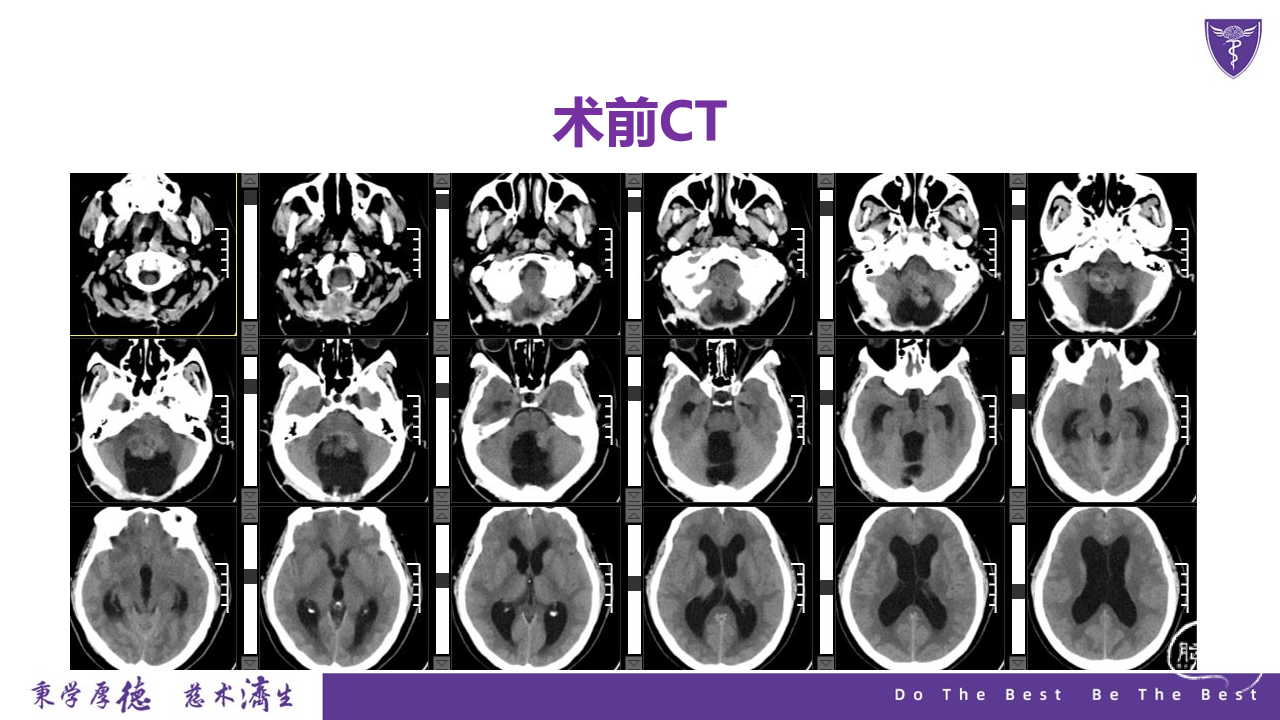

王杰教授团队:四脑室复发室管膜瘤切除术